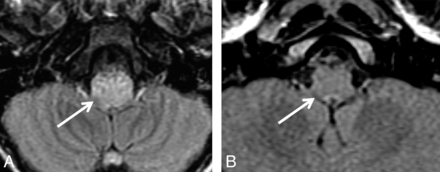

Case 5. Axial FLAIR image (A) demonstrates increased T2 signal in the medulla oblongata (arrow). Twelve-month follow-up shows complete resolution of the lesion (arrow, B).